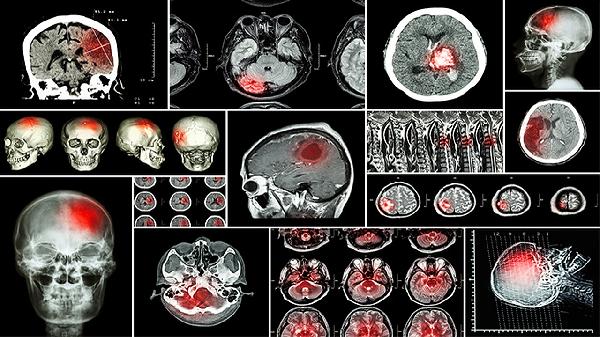

孩子颅内感染初期症状主要有发热、头痛、呕吐、精神萎靡、颈部僵硬等。颅内感染通常由病毒、细菌、真菌等病原体引起,需及时就医明确病因。